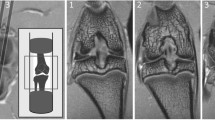

The sham rats showed significantly higher BV (13 %), BV/TV ratio (18 %) bone surface (11 %), trabecular number (14 %) and connectivity diameter (21 %) and a lower trabecular separation index (24 %) compared to the MMT rats (Table 2; Fig. 2).

Two-dimensional µCT image of the proximal tibia from sham and MMT rat. Cortical and cancellous bone was measured for the entire epiphysis (E), whereas cancellous bone was evaluated at the metaphysis in the area of secondary spongiosa (M). Solid arrow indicates a lesser amount of cancellous bone in MMT rat; dotted arrow indicates thickening of the subchondral bone in MMT rat; arrowhead indicate osteophyte formation in MMT rat. Dotted blue square indicates area of epiphysis where UV micrographs are taken to show the new bone formation. Arrowheads indicate intensive bone remodeling of the osteophyte in MMT rat as judged by the presence of both calcein and alizarin red dye, whereas there is no osteophyte formation in the sham rat

Bone dynamic

Dynamic histology revealed active bone remodeling and active osteophyte formation at the medial epiphysis of the MMT rats compared to the sham rats, whereas at the tibial metaphysis, the sham rats exhibited more bone formation and more cancellous bone than the MMT rats (Fig. 2).